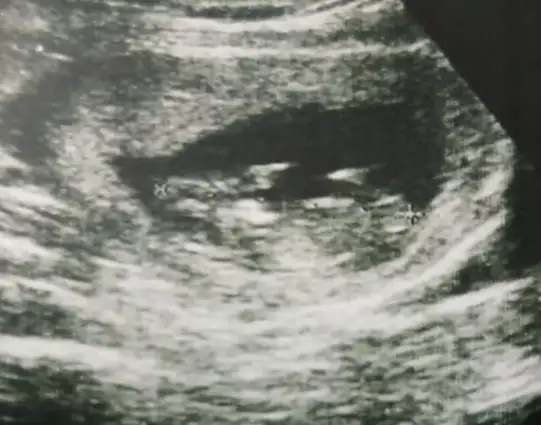

Ben kafa yapısı ve duruşa göre dedim nub tan anlayanları dikkate al derimAy evetemin misin nub falan baktın mı güzelce

Tipi bana da erkek gibi geldi ama nub işini hiç anlamıyorumBen kafa yapısı ve duruşa göre dedim nub tan anlayanları dikkate al derim![]()